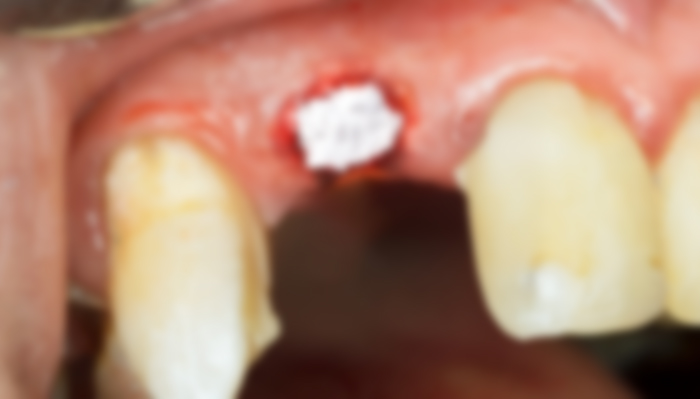

발치와 보존술

발치와 보존술은 치조제 보존술이라고도 불리웁니다. 일반적으로 수술과 동시에 뼈이식은 동시에 이루어 지지만, 발치 후 수술이 불가능한 경우 수술이 몇 개월 후에 독립적으로 이루어 집니다. 이럴 경우 발치와의 수축을 방지하기 위하여 발치와에 골이식을 하는 발치와 보존술을 진행합니다.